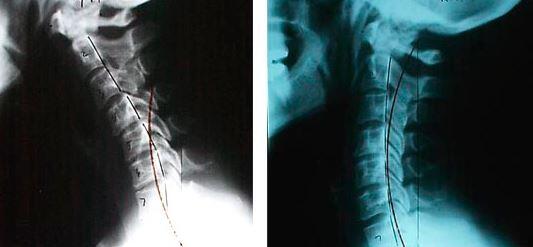

Boyun bölgesinde 7 adet vertebra vardır bu vertebralar yandan tepe noktası boynun ön bölgesi olan ’C ‘ harfini andırır. Boyun bölgesindeki omurga eğriliğini servikal lordoz olarak ifade ediyoruz. Bu eğri tamamen normaldir ve aslında arzu ederiz, çünkü kafa ve omurganın stabilize edilmesine yardımcı olur. Fakat eğrinin düzleşmesi yani fizyolojik lordoz olarak ifade ettiğimiz açının azalması yada kaybolup ’ I ‘ şeklini alması durumunda boyun düzleşmesi olarak ifade ettiğimiz klinik tablo ile karşı karşıya kalırız. Hatta bu eğri daha da ilerleyip tersine açılanma gösterirse tablonun daha ciddi bir hal alması söz konusudur.